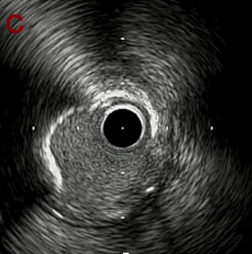

IVUS after OAS low speed 3回

IVUS imaging after low speed 3回

OAS low speedによる引きのsandingを3回行いIVUSを確認するとa-cでは心筋側側へのOASによる良好なbias変化と、それに伴いdの健常側への危険なbias変化を認めた。

そのためcでIVUSマーキングを行い、その点より引きで赤線のpinpoint OAS high speedを行い、dに関してはinjury回避のためにOASを当てない方針とした。